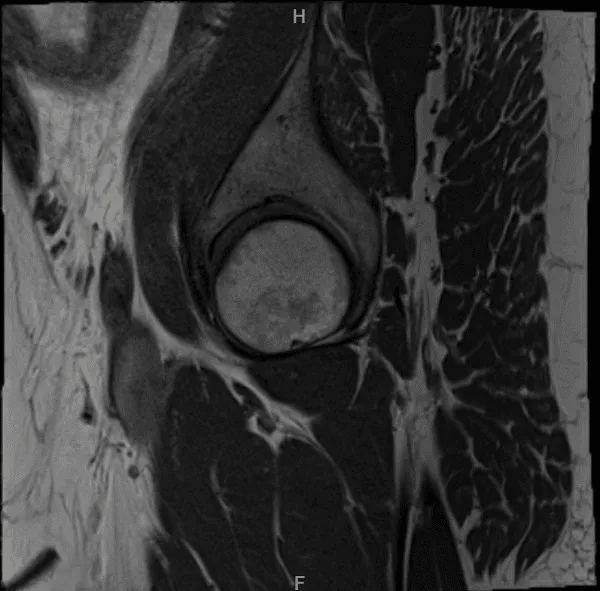

A 59-year-old patient visited our office with complaints regarding pain on the inner side of his right knee as well as outside of the right hip. We did the MRI of the hip and the knee, which showed medial root tear of the right knee and trochanteric bursitis of the right hip.

MRI Right hip non-contrast

MRI Right knee non-contrast